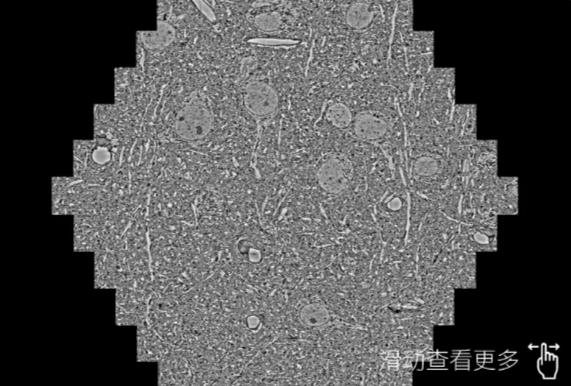

鼠脑切片。左图使用株洲蔡司株洲扫描电镜MultiSEM706对165μmx143pm面积区域成像,耗时仅需1.5秒。右图为鼠脑切片中30μm区域放大效果。样品由芝加哥大学B.Kasthuri提供。